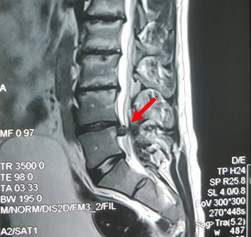

Интересно, что проведённая перед операцией МРТ никаких странностей не показала. Была диагностирована грыжа межпозвонкового диска, которая показана внизу.